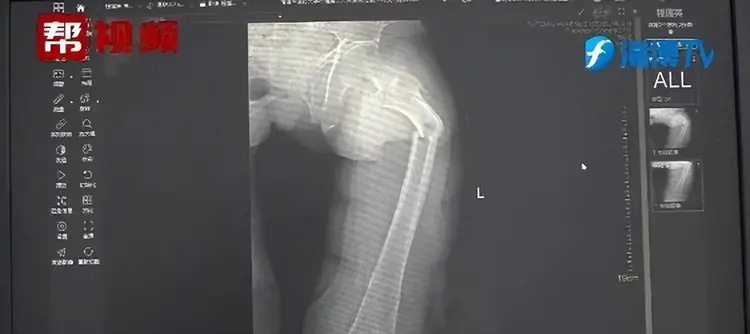

Phim chụp X-quang cho thấy anh Ye bị gãy xương đùi. Các bác sĩ khi đó cũng chưa thể chứng minh rằng cơn ho của anh có ảnh hưởng gì đến chấn thương vật lý này.

Phim chụp X-quang của bệnh nhân. Ảnh: O.C